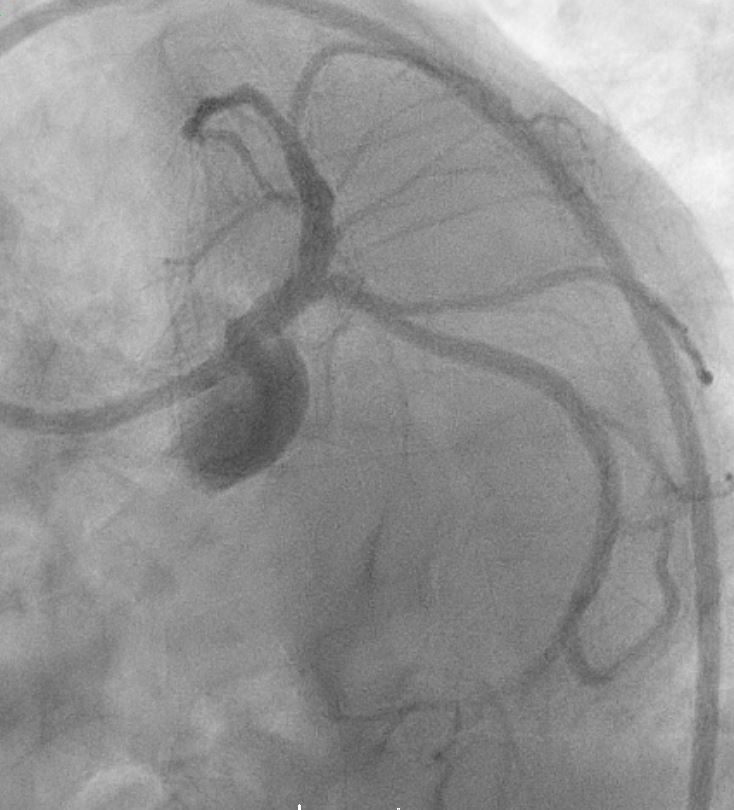

Coronary angiogram shows severe disease ostio-proximal LAD with severe calcification/calcium nodule , mild disease left circumflexsevere stenosis proximal and mid RCA -recessive

Right Radial approach, Slender 6/7Fr , EBU 3.5 7FR changedto EBU 3.0 7FR Sion blue to LCX, Run-through floppy to LAD IVUS run to LAD Fibro calcified lesion ostial LAD - calcium arc 180 degrees with calcium nodule, ostial LAD 3.48mm2 , tightest proximal LAD 2.31mm2 distallumen size 3.0mm and proximal 3.5mm and ostial 4.0mm ostial LM MLA 10.8mm Used microcatheter fine cross to LAD , Exchange with balloon trapping withRotaWireRotablator 1.5burr introduced- 2 runs high speed 180kph and2 runs at 80kph IVUS done post Rotablator - tightest proximal LAD 2.31mm2 -->3.22mm2 , ostial LAD 3.48mm2 -->4.51mm2 Predilate further NC 3.5x15mm up to 16atm Stented Synergy monorail 3.0x32mm body LM to proximal LAD at11atm with guide plus 6FRpost dilated NC 3.5x12mm up to 20atm Guiding catheter slipped out and lost the system, tried to reengage but challenging thus decided to change to right femoral puncture to use EBU3.5/7fr ,post dilate LM-LAD NC 4.0/12mm 6atmOstial LCX pinched - decided for Kissing balloon inflation and DCB LCX ostium predilated Ostial LCX 2.75x15mm up to 8atm Kissing inflation performed with NC emerge 3.5X15mm LAD, NC2.75x12mm in LCX 8atm DCB AGENT MONORAIL 2.75X15 MM 8atm 60seconds to ostial LCX last POT with NC 4.0x12mm up to 16atm IVUS done stent well opposed, Ostial LAD MSA 8.25mm2Proximal MSA 5.64mm2 TIMI III flow

In summary, this was a complex PCI for a severely fibro-calcified ostial and proximal LAD lesion with significant calcium arc and a calcium nodule confirmed on IVUS. Despite initial right radial access with a Slender 6/7 Fr system, guide support with EBU 3.5 and later EBU 3.0 remained suboptimal, ultimately necessitating conversion to a right femoral 7 Fr approach for adequate support. Overall, the case highlights the importance of adaptive access strategy, aggressive plaque modification, IVUS-guided optimization, and bifurcation management to achieve an excellent final physiological and angiographic result in a heavily calcified LM–LAD lesion.